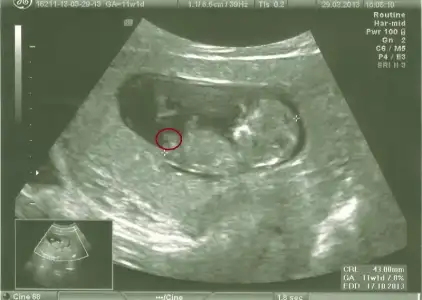

dr soylemeden siz gorun genital nub teorisi ( bebegin cinsiyeti)

orkidecim canım bu kırmızıyla işaretlediğim yer nub çıkıntısı mı ayak mı

bence nub çıkıntısı, sen ne dersin, sen daha iyi bilirsin tabii canım

ayak diyor snnemlerde bence ayak değil ayağı yukarda sanki

Yukarıda olan bacak yuvarlak içine aldım ama görünüyor mu acaba?:18:

canım birtanesi bacak yukarıda olan.doktor çizdi hatta altta.Gerçi bacak anlaşılıyor değil mi ?o zaman demek ki kız

paralel olup erkek cikanda cok oldu bak gecenki fotosuda dikeydi

ama hakikattenn nub cok buyuk erkege donecek nublar gibi ama asagida olmasi beni huzunlendiriyor :5::5::5:

yaaa bak o cizdigin yuvarlagin altinda hemen dikey kucuk bir cikinti var eger oysa ki insallahh diyeelim o zaman kesin erkekk :43:yaa iki cikintisi var bebegin